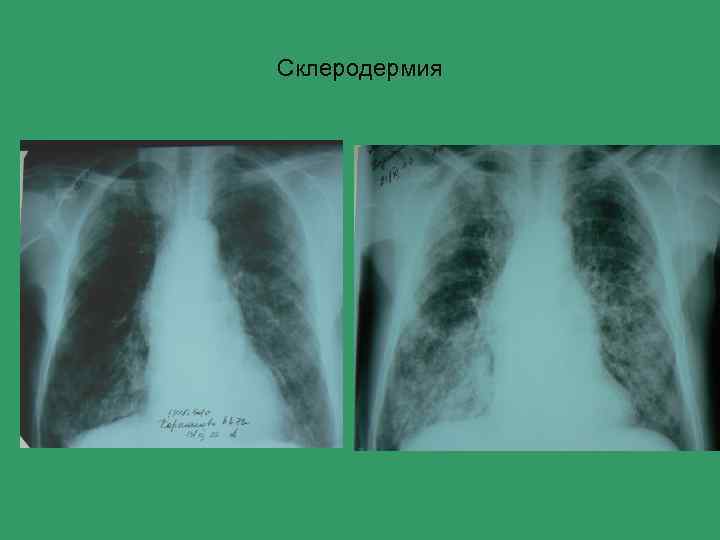

Склеродермия